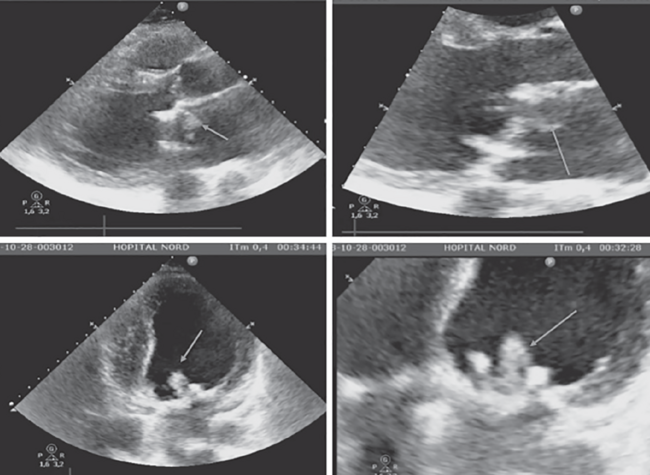

Angiographic study showed an occlusion of the circumflex artery on a bifurcation site with a marginal branch (Figure 3A). A 0.014˝ Balance Middleweight guidewire (Abbott Vascular) was used and coronary aspiration in both the marginal and circumflex branches with a 7 Fr Export aspiration catheter (Medtronic) was performed via the guiding catheter, which allowed embolic debris to be removed (Figure 3B). After repeated aspiration attempts, we observed TIMI 2 flow restoration in the marginal branch with a persistent occlusion of the circumflex artery. Kissing-balloon inflation with two 3.0 x 20 mm Ryujin Plus RX semicompliant balloons (Terumo) was use to restore complete revascularization of the circumflex coronary territory (Figures 3C and 3D). Histological examination of the debris (Figure 4) concluded that it was a part of the vegetation that had embolized.